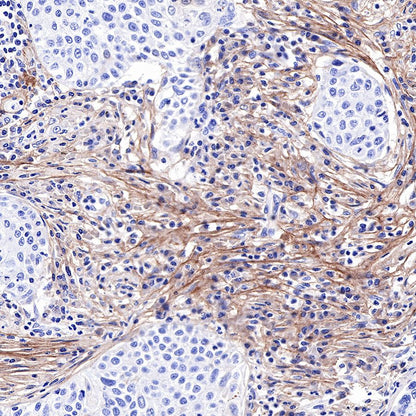

IHC shows positive staining in paraffin-embedded human stomach. Anti-COL3A1(PIIINP) antibody was used at 1/500 dilution, followed by a HRP Polymer for Mouse & Rabbit IgG (ready to use). Counterstained with hematoxylin. Heat mediated antigen retrieval with Tris/EDTA buffer pH9.0 was performed before commencing with IHC staining protocol.